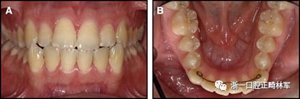

一顆或兩顆尖牙位置的橫向變化可能發生在與每顆牙齒粘合的小弓絲上,并且在極軟弓絲(圖3)和柔性螺旋弓絲(圖4)上都可以看到。較大直徑的弓絲會產生不同類型的橫向變化。較硬的弓絲與更小的弓絲相比,在尖牙之間產生更多的相關關系。弓絲的扭曲會導致尖牙的往復運動和弓形的歪斜(圖5)。相對較硬弓絲的向下偏斜可以通過尖牙產生擴張(圖6)。

圖3.極軟弓絲完全完好,在多個空間平面上的拱形歪斜,右側尖牙的面部傾斜以及右側側切牙和中切牙在相反方向上的扭矩:A,頰面視圖; B,咬合面視圖。

正畸文獻閱讀--固定舌側保持器作用下意外的牙齒移動

圖4柔軟的螺旋弓絲保持器,下頜右側尖牙嚴重的舌側傾斜以及下頜左側尖牙的唇側移位:A,正面視圖; B,咬合面視圖(John Iaculli博士提供)。